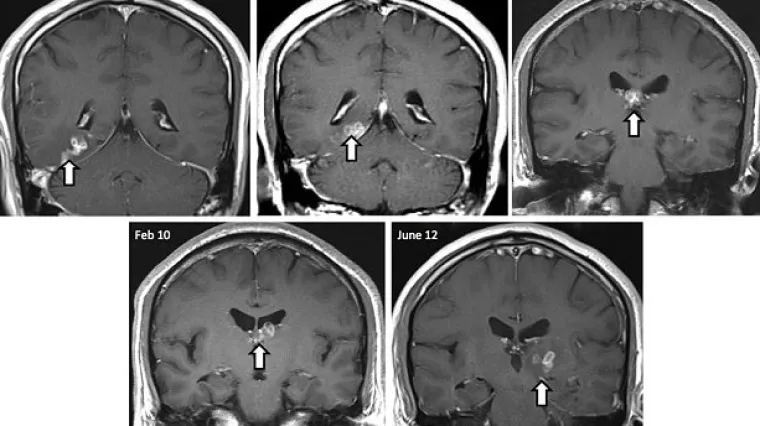

Crv živio u mozgu Britanca i zadavao mu glavobolje!

Centimetar dug crv izvučen je iz mozga Britanca koji se liječniku požalio na glavobolje, objavili su u petak znanstvenici i otkrili da je životinjica Spirometra erinaceieuropei četiri godine obitavala u mozgu 50-godišnjeg muškarca i selila se s jedne strane na drugu.

Stručnjaci su rekli da je takav parazit prvi put otkriven u Velikoj Britaniji, a od 1953., zabilježeno je 300 takvih slučajeva u svijetu.

Crv izaziva upalu tkiva te gubitak pamćenja i glavobolje ako se nastani u mozgu.